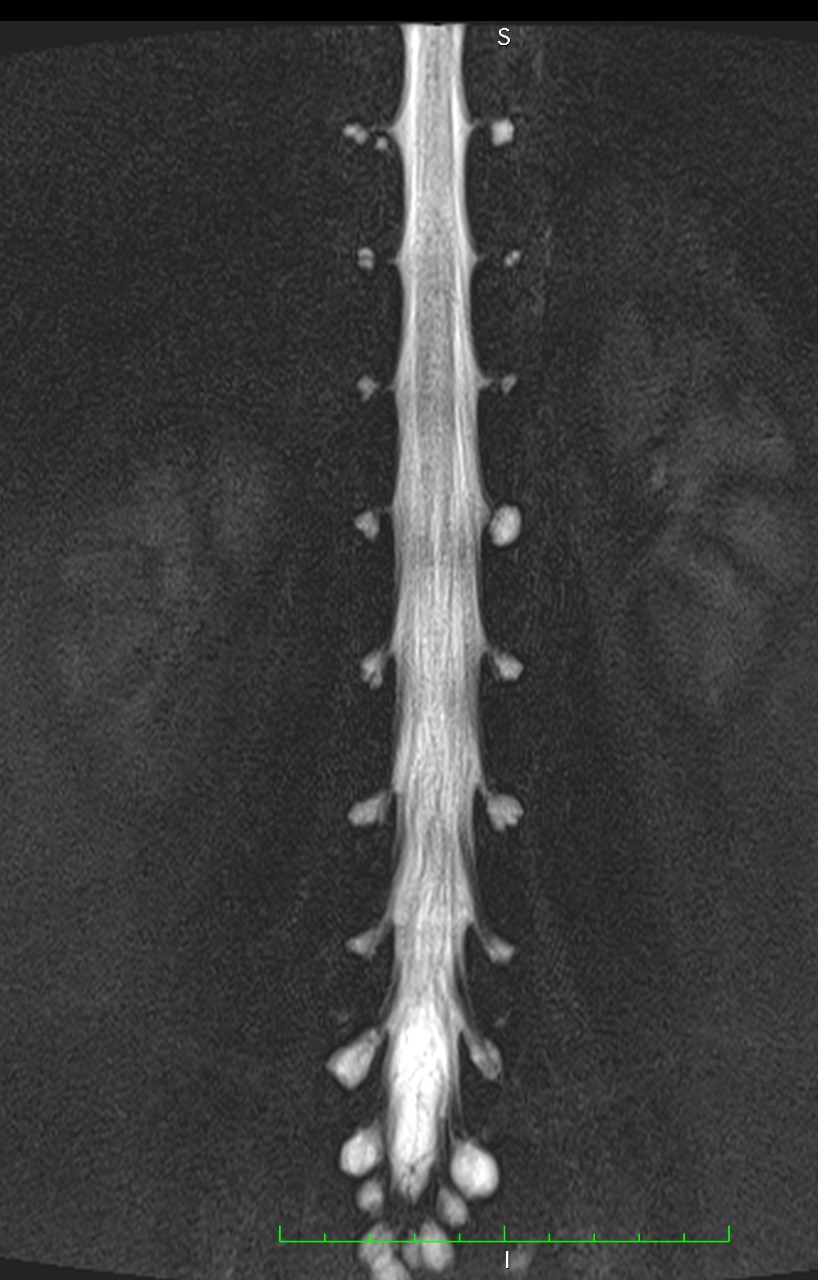

Resonancia Magnética de columna lumbar

“QUISTES PERINEURALES”

Los quistes perineurales son quistes llenos de líquido cefalorraquídeo en las raíces nerviosas, localizados principalmente en la zona sacra de la columna vertebral, aunque pueden encontrarse en cualquier sección de la columna vertebral; pueden causar una radiculopatía progresivamente dolorosa. Las mujeres se ven afectadas con mayor frecuencia que los hombres. Los pacientes con quistes perineurales presentan dolor en la zona de los nervios afectados por el quiste, debilidad muscular, dificultad para sentarse durante periodos prolongados, pérdida de la sensibilidad, pérdida de reflejos, dolor al estornudar o toser, inflamación en la zona sacra, parestesias, dolor de cabeza, ciática, y disfunción intestinal, de vejiga y sexual.

El diagnóstico se basa en la resonancia magnética.